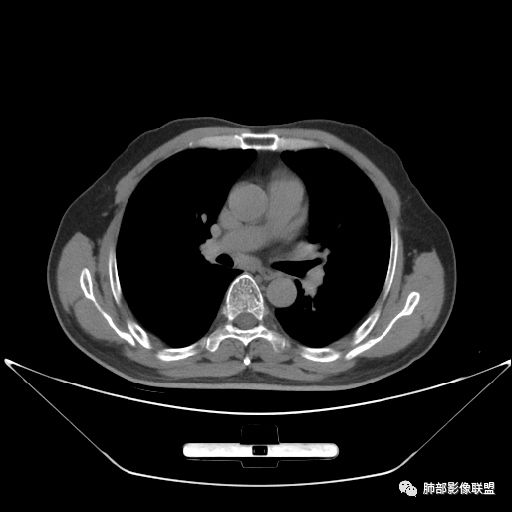

入院CT